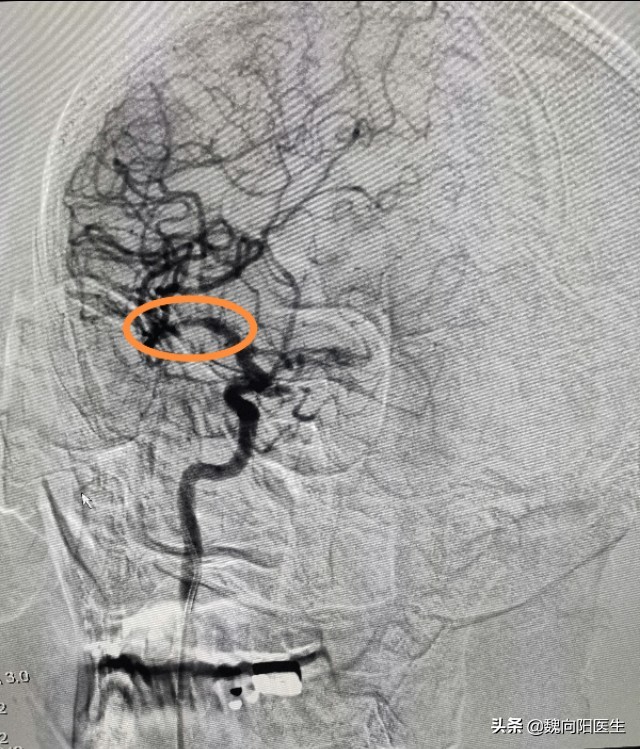

转入神经科之后,立即给安排的脑血管造影检查。

果然如医生所料,患者的脑血管确实存在大问题。脑血管造影提示:右侧大脑中动脉中度狭窄,且动脉斑块不规则。